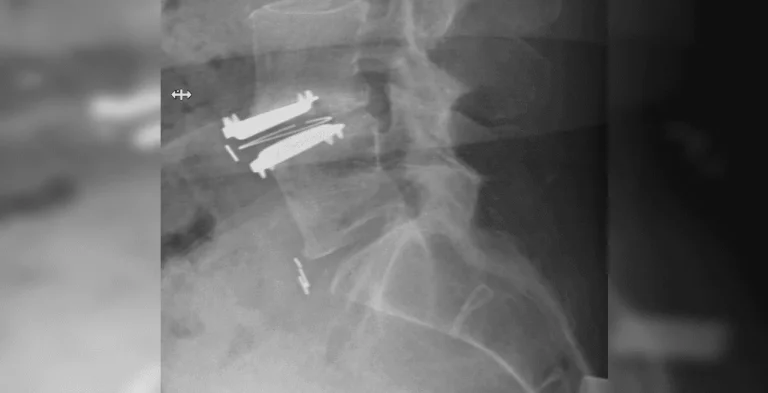

X-ray of a spine with metal screws and plates inserted.

X-ray of a neck showing metal screws and plates in the cervical spine.